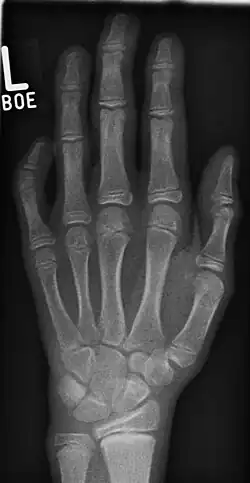

Klinodaktylie

Unter Klinodaktylie versteht man allgemein die in der Regel angeborene seitlich-winklige Abknickung eines Fingerglieds im Handskelett. Man unterscheidet die

- Klinoteledaktylie: Abwinklung im Endgelenk (Distales Interphalangealgelenk)

- Klinomesodaktylie: Abwinklung im Mittelgelenk (Proximales Interphalangealgelenk)

- Klinobasodaktylie: Abwinklung im Grundgelenk (Metacarpophalangealgelenk)